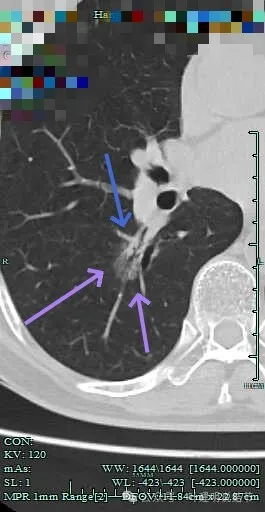

病灶出现,淡磨玻璃密度,但轮廓较清,且表面不平。

病灶内部有走行的支气管,但显得有些僵硬;病灶表面有浅分叶。

灶内血管走行,轮廓与边界清楚。

边缘有毛刺征!

沿支气管走行方向延伸,磨玻璃密度,且支气管内壁显得毛糙。

毛刺明显,轮廓清楚,灶内支气管扩张通气。

毛刺明显,灶内有实性成分出现。

毛刺征明显!!灶内密度杂乱。

实性成分较多,边缘毛刺。

毛刺征明显,而且是短毛刺且锐利。

毛刺。

边缘区也不光滑,显毛糙。

靶重建显示混合密度,边缘毛糙,内部杂乱,灶内支气管通气且僵硬。

病灶影响到斜裂肺门部,边缘毛刺明显。灶内支气管僵硬。

密度杂乱,毛刺明显,支气管僵硬。

杂乱密度,整体轮廓较清,边缘毛糙。

斜裂根部有增厚并与病灶连着。考虑是肿瘤已经侵及叶间裂。

病灶边缘毛刺明显。